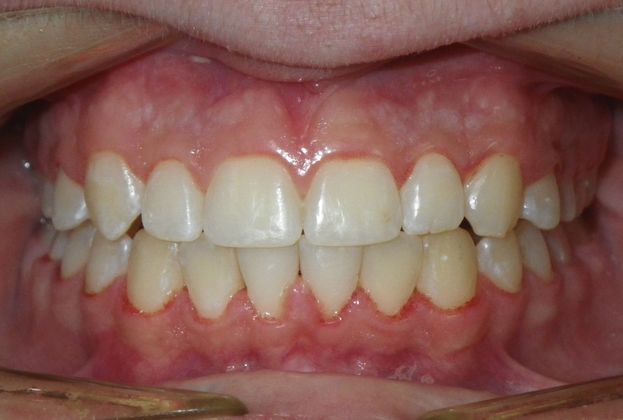

This patient had an upper right permanent cuspid that was impacted and would need uncovering by oral surgeon who would place bracket with chain to help enable us to tease the permanent cuspid into its proper position. She also had a permanent 2nd Molar that was impacted due to improper development of 3rd molars and the oral surgeon could remove them at the same time as uncovering of the permanent cuspid. After uncovering and removal of lower 3rd molars, we would begin comprehensive straight wire orthodontic treatment.